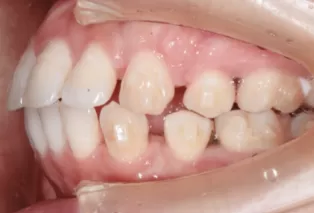

Photos intra-orales